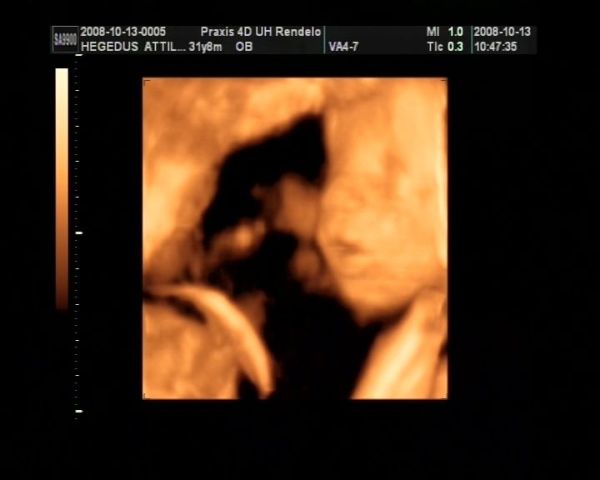

Ez tegnapi